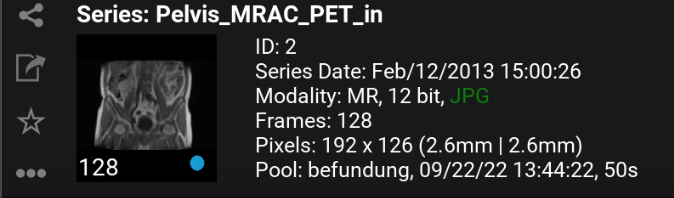

9.2. Series selection

Datasets: Enumeration of all recorded images of the study of a patient.

By clicking a series it will be downloaded (if it’s not already downloaded) and opened for viewing.

9.2.2. Series details

More details about a series can be foun the series selection list.

Pool: name of pool; time when the series was available in mRay; transfer time from PACS to mRay